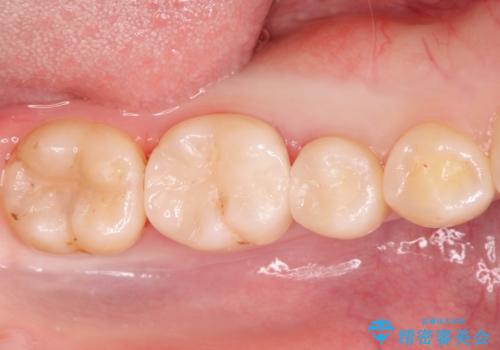

自然な見た目のセラミックインレー

セラミックインレーによる修復を行っております。

自然な見た目に満足して頂きました。

保険治療で使える材料には制限があり、見た目だけでなく精度でも劣ります。当院でのセラミックインレーは歯とのつなぎ目を拡大鏡で確認して精度高く仕上げるため、むし歯のリスクを限りなく少なくできるよう治療します。